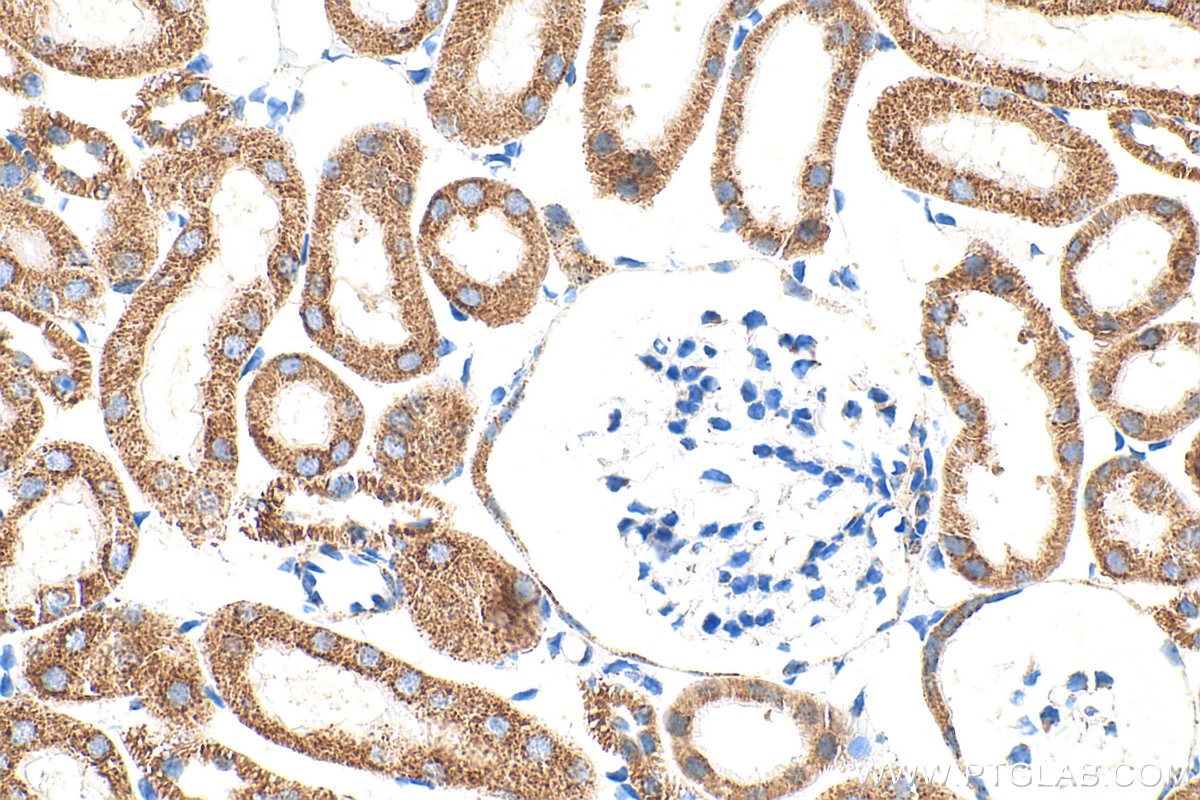

| Positive IHC detected in | human liver cancer tissue, human heart tissue, human kidney tissue, human testis tissue, human liver tissue Note: suggested antigen retrieval with TE buffer pH 9.0; (*) Alternatively, antigen retrieval may be performed with citrate buffer pH 6.0 |

| Immunohistochemistry (IHC) | IHC : 1:500-1:2000 |